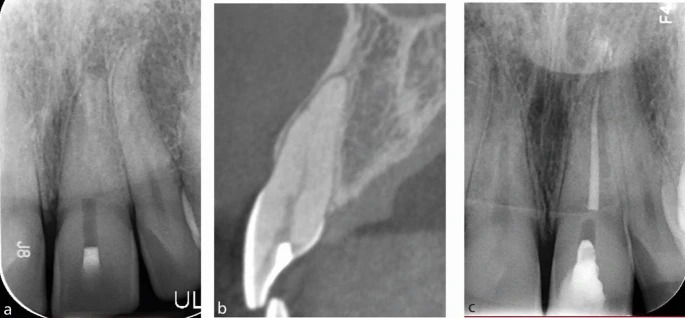

Пример: на рисунке 8 показан зуб 21, направленный на лечение после неудачной попытки нахождения канала.

a) Предоперационная прицельная рентгенограмма зуба 21, на которой видно неудачное формирование полости доступа, выполненное врачом общей практики.

b) Сагиттальный срез КЛКТ демонстрирует чётко выраженный канал, отходящий от нёбной стороны существующей полости доступа.

c) Прицельная рентгенограмма после завершённого эндодонтического лечения зуба 21: канал обтурирован гуттаперчей и запечатан модифицированным смолой стеклоиономерным цементом; зуб подготовлен к внутреннему/наружному отбеливанию. Канал был успешно локализован с использованием микроскопа и данных КЛКТ.

По прицельной рентгенограмме канал не определялся, но CBCT отчётливо показала его положение, позволив сориентировать направление препарирования. Используя эти данные и микроскоп, врач быстро нашёл канал, при этом потери твёрдых тканей были минимальны. Этот случай демонстрирует диагностическую ценность CBCT — особенно после неудачного первичного доступа, когда можно скорректировать направление препарирования. Кроме того, программные инструменты CBCT позволяют точно измерить глубину доступа и контролировать ориентацию инструмента.